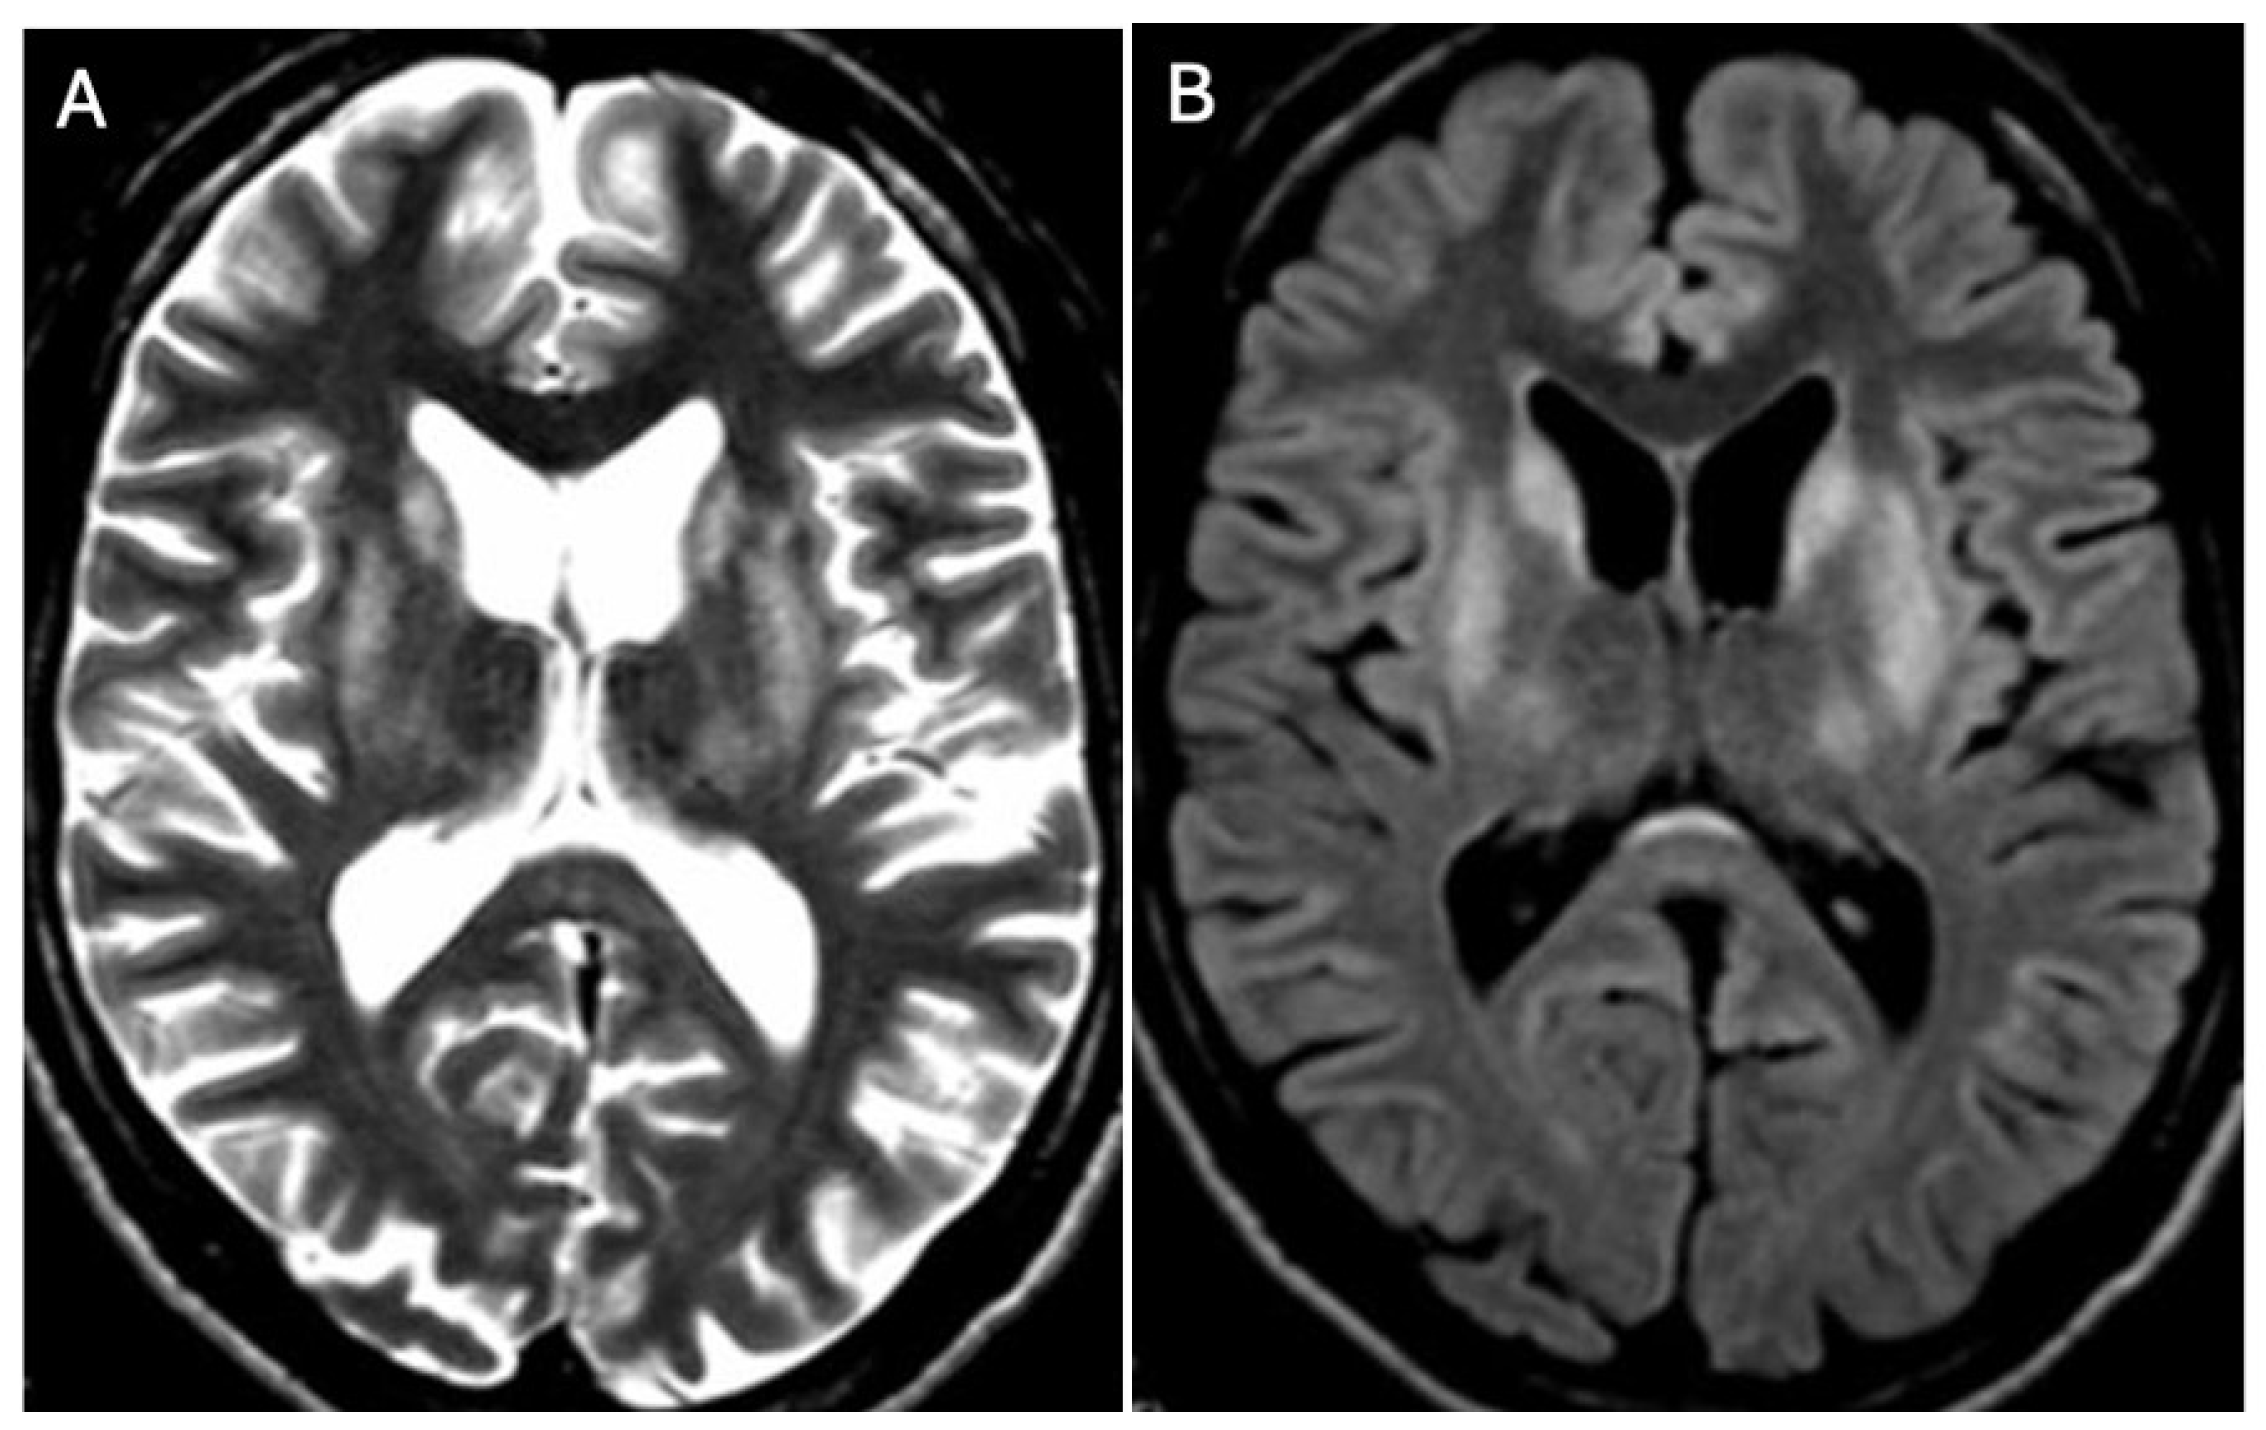

3.1. Classical Brain MRI Examination in WD Patients